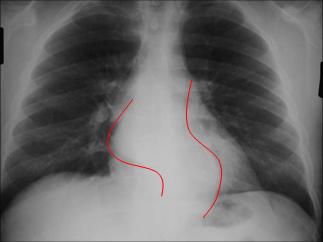

Aortic contour and azygo-esophageal

recess abnormal